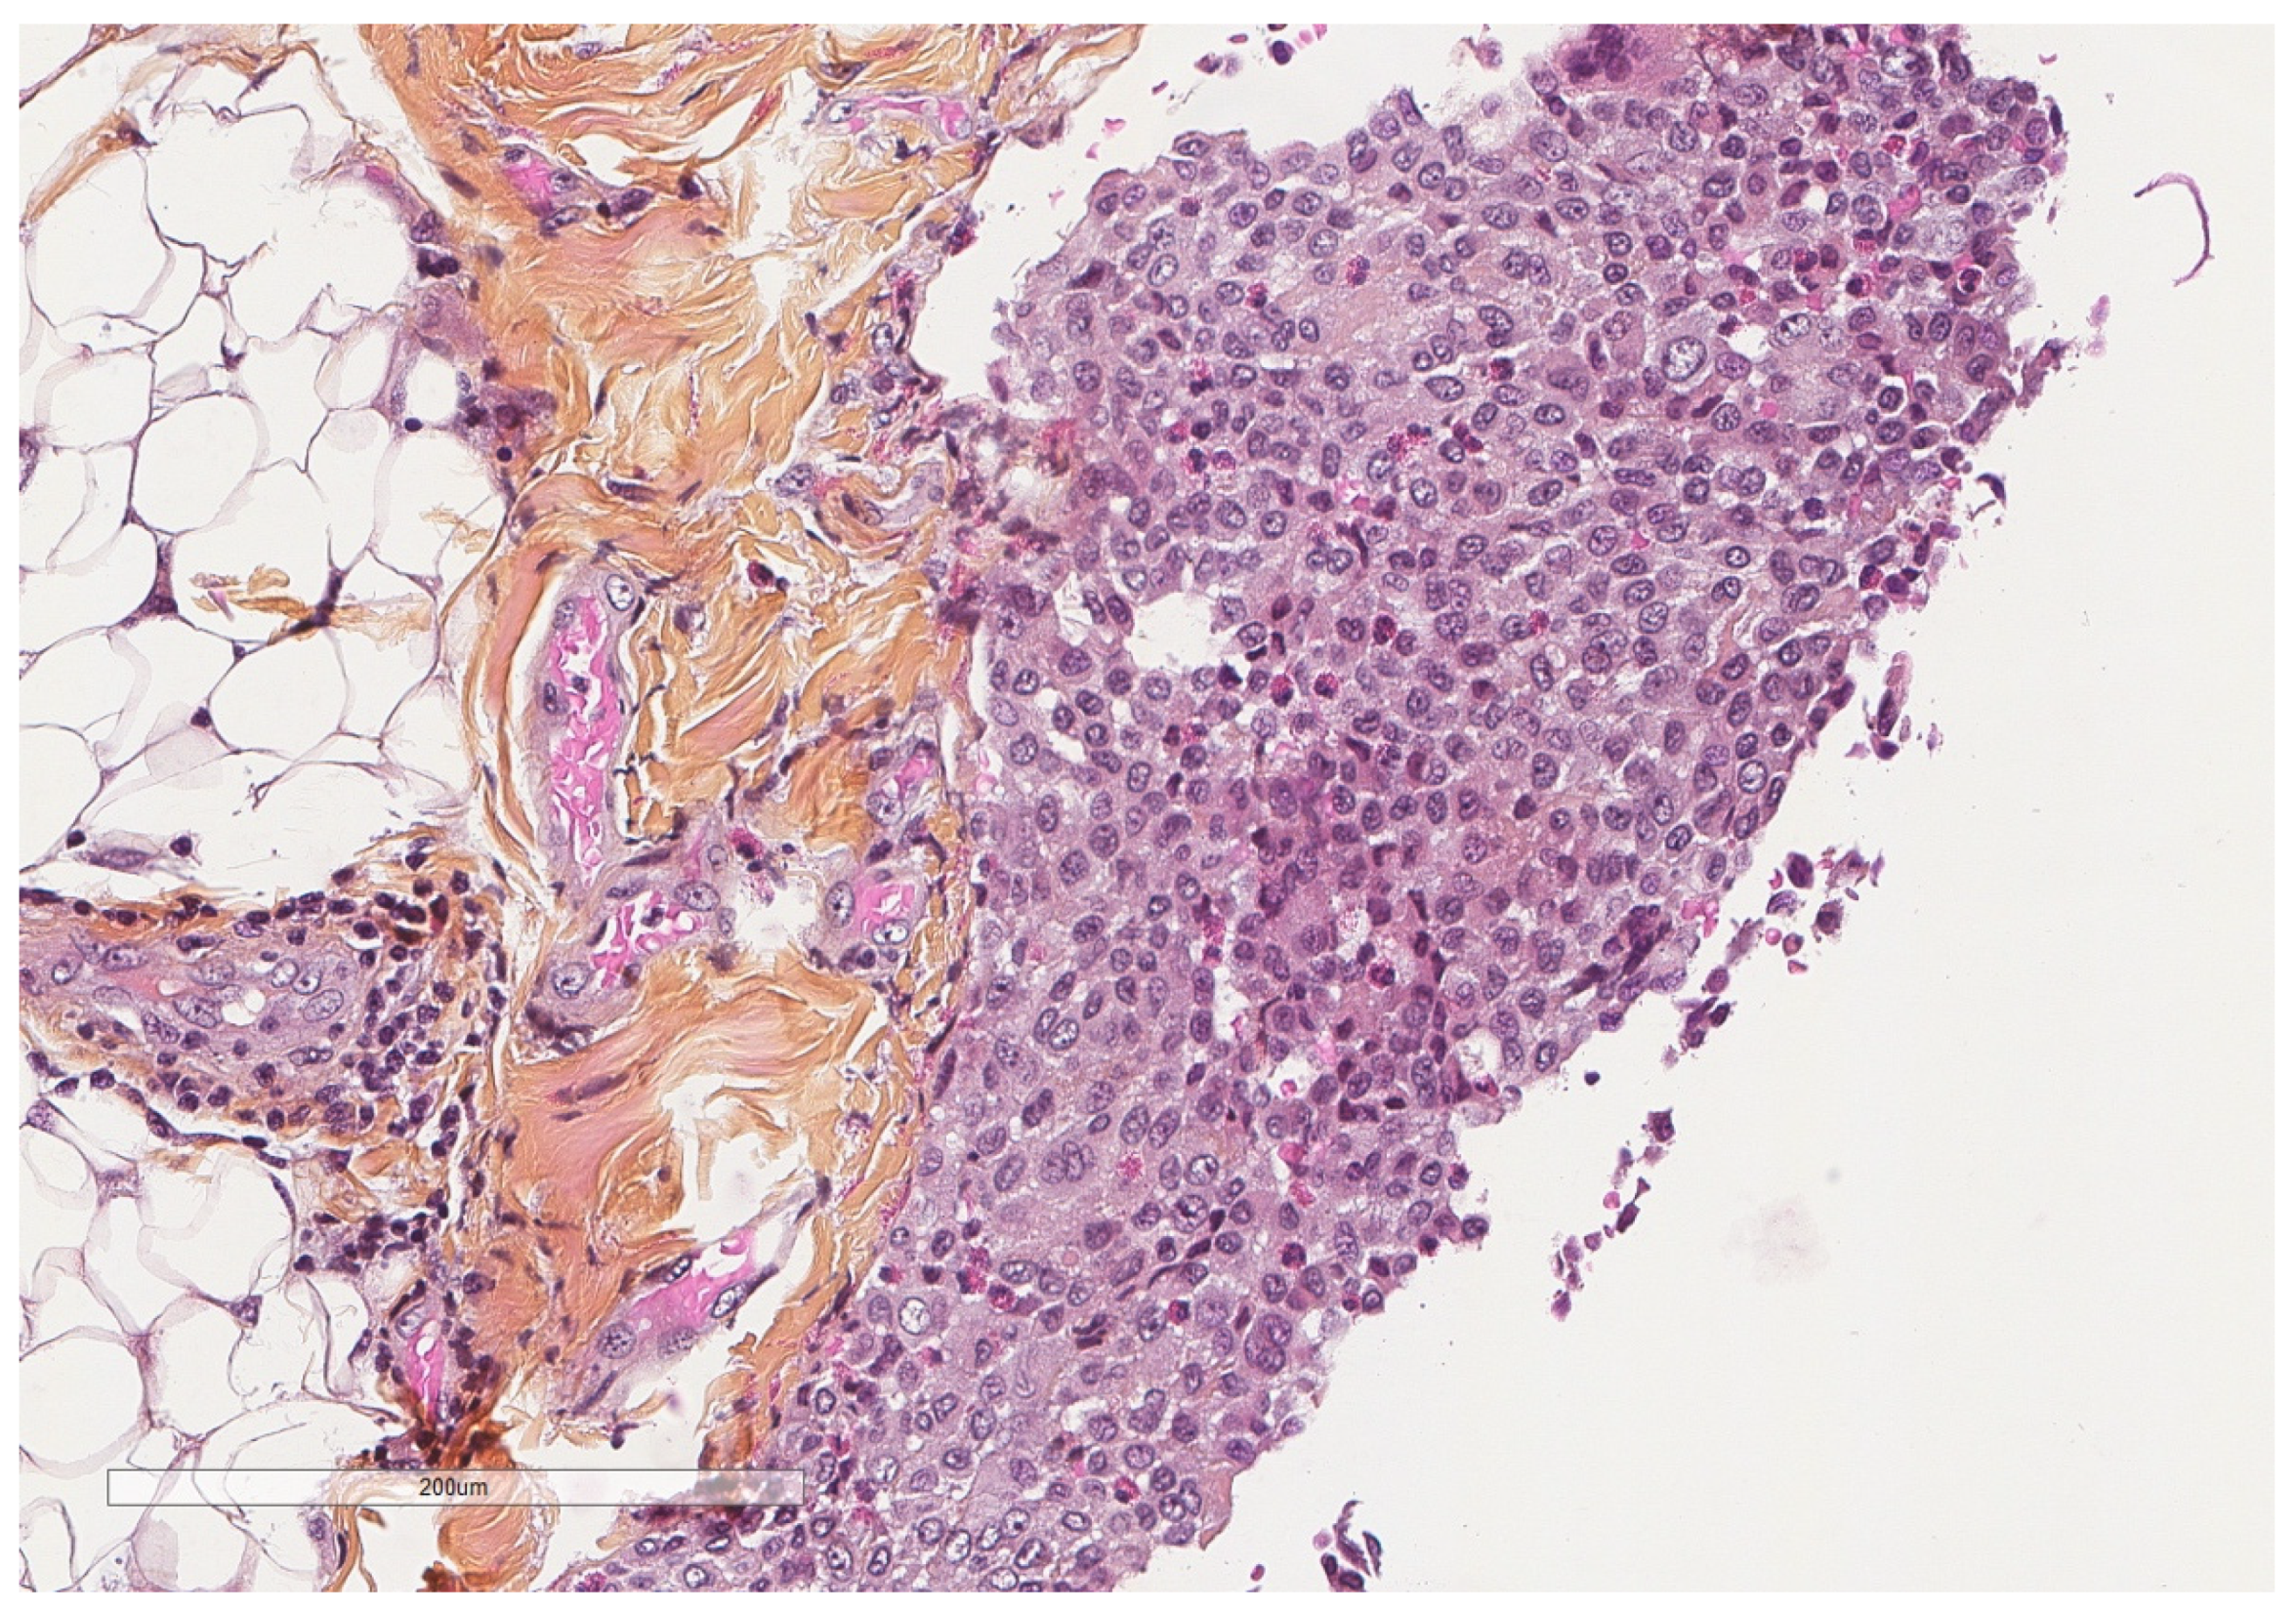

- Karpathiou, G.; Hathroubi, S.; Patoir, A.; Tiffet, O.; Casteillo, F.; Brun, C.; Forest, F.; Rahman, N.M.; Peoc’h, M.; Froudarakis, M.E. Non-specific pleuritis: Pathological patterns in benign pleuritis. Pathology 2019, 51, 405–411. [Google Scholar] [CrossRef] [PubMed]